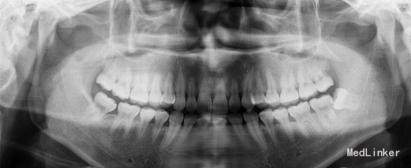

患者女,25 主诉: 要求拔牙。 现病史: 3天前,患者感左下后牙疼痛,食物嵌塞,咀嚼不适。自服消炎药后好转,前来就诊。 既往史: 体健,否认药敏史。

检查: 18.28颌面龋坏,质地软,牙颈部脱矿,叩诊(-),不松动。 37玻璃充填物,叩诊(-),不松动,冷热刺激正常。 38近中水平阻生,牙龈无红肿,叩诊(-),探诊有盲袋,盲袋内食物碎屑。 47缺失多年,48近中向移位,间隙1mm,叩诊(-),不松动。

治疗计划:18、28,38拔除。 37重新充填。 48观察。 治疗:28局麻下拔除。 38阻滞下拔除。